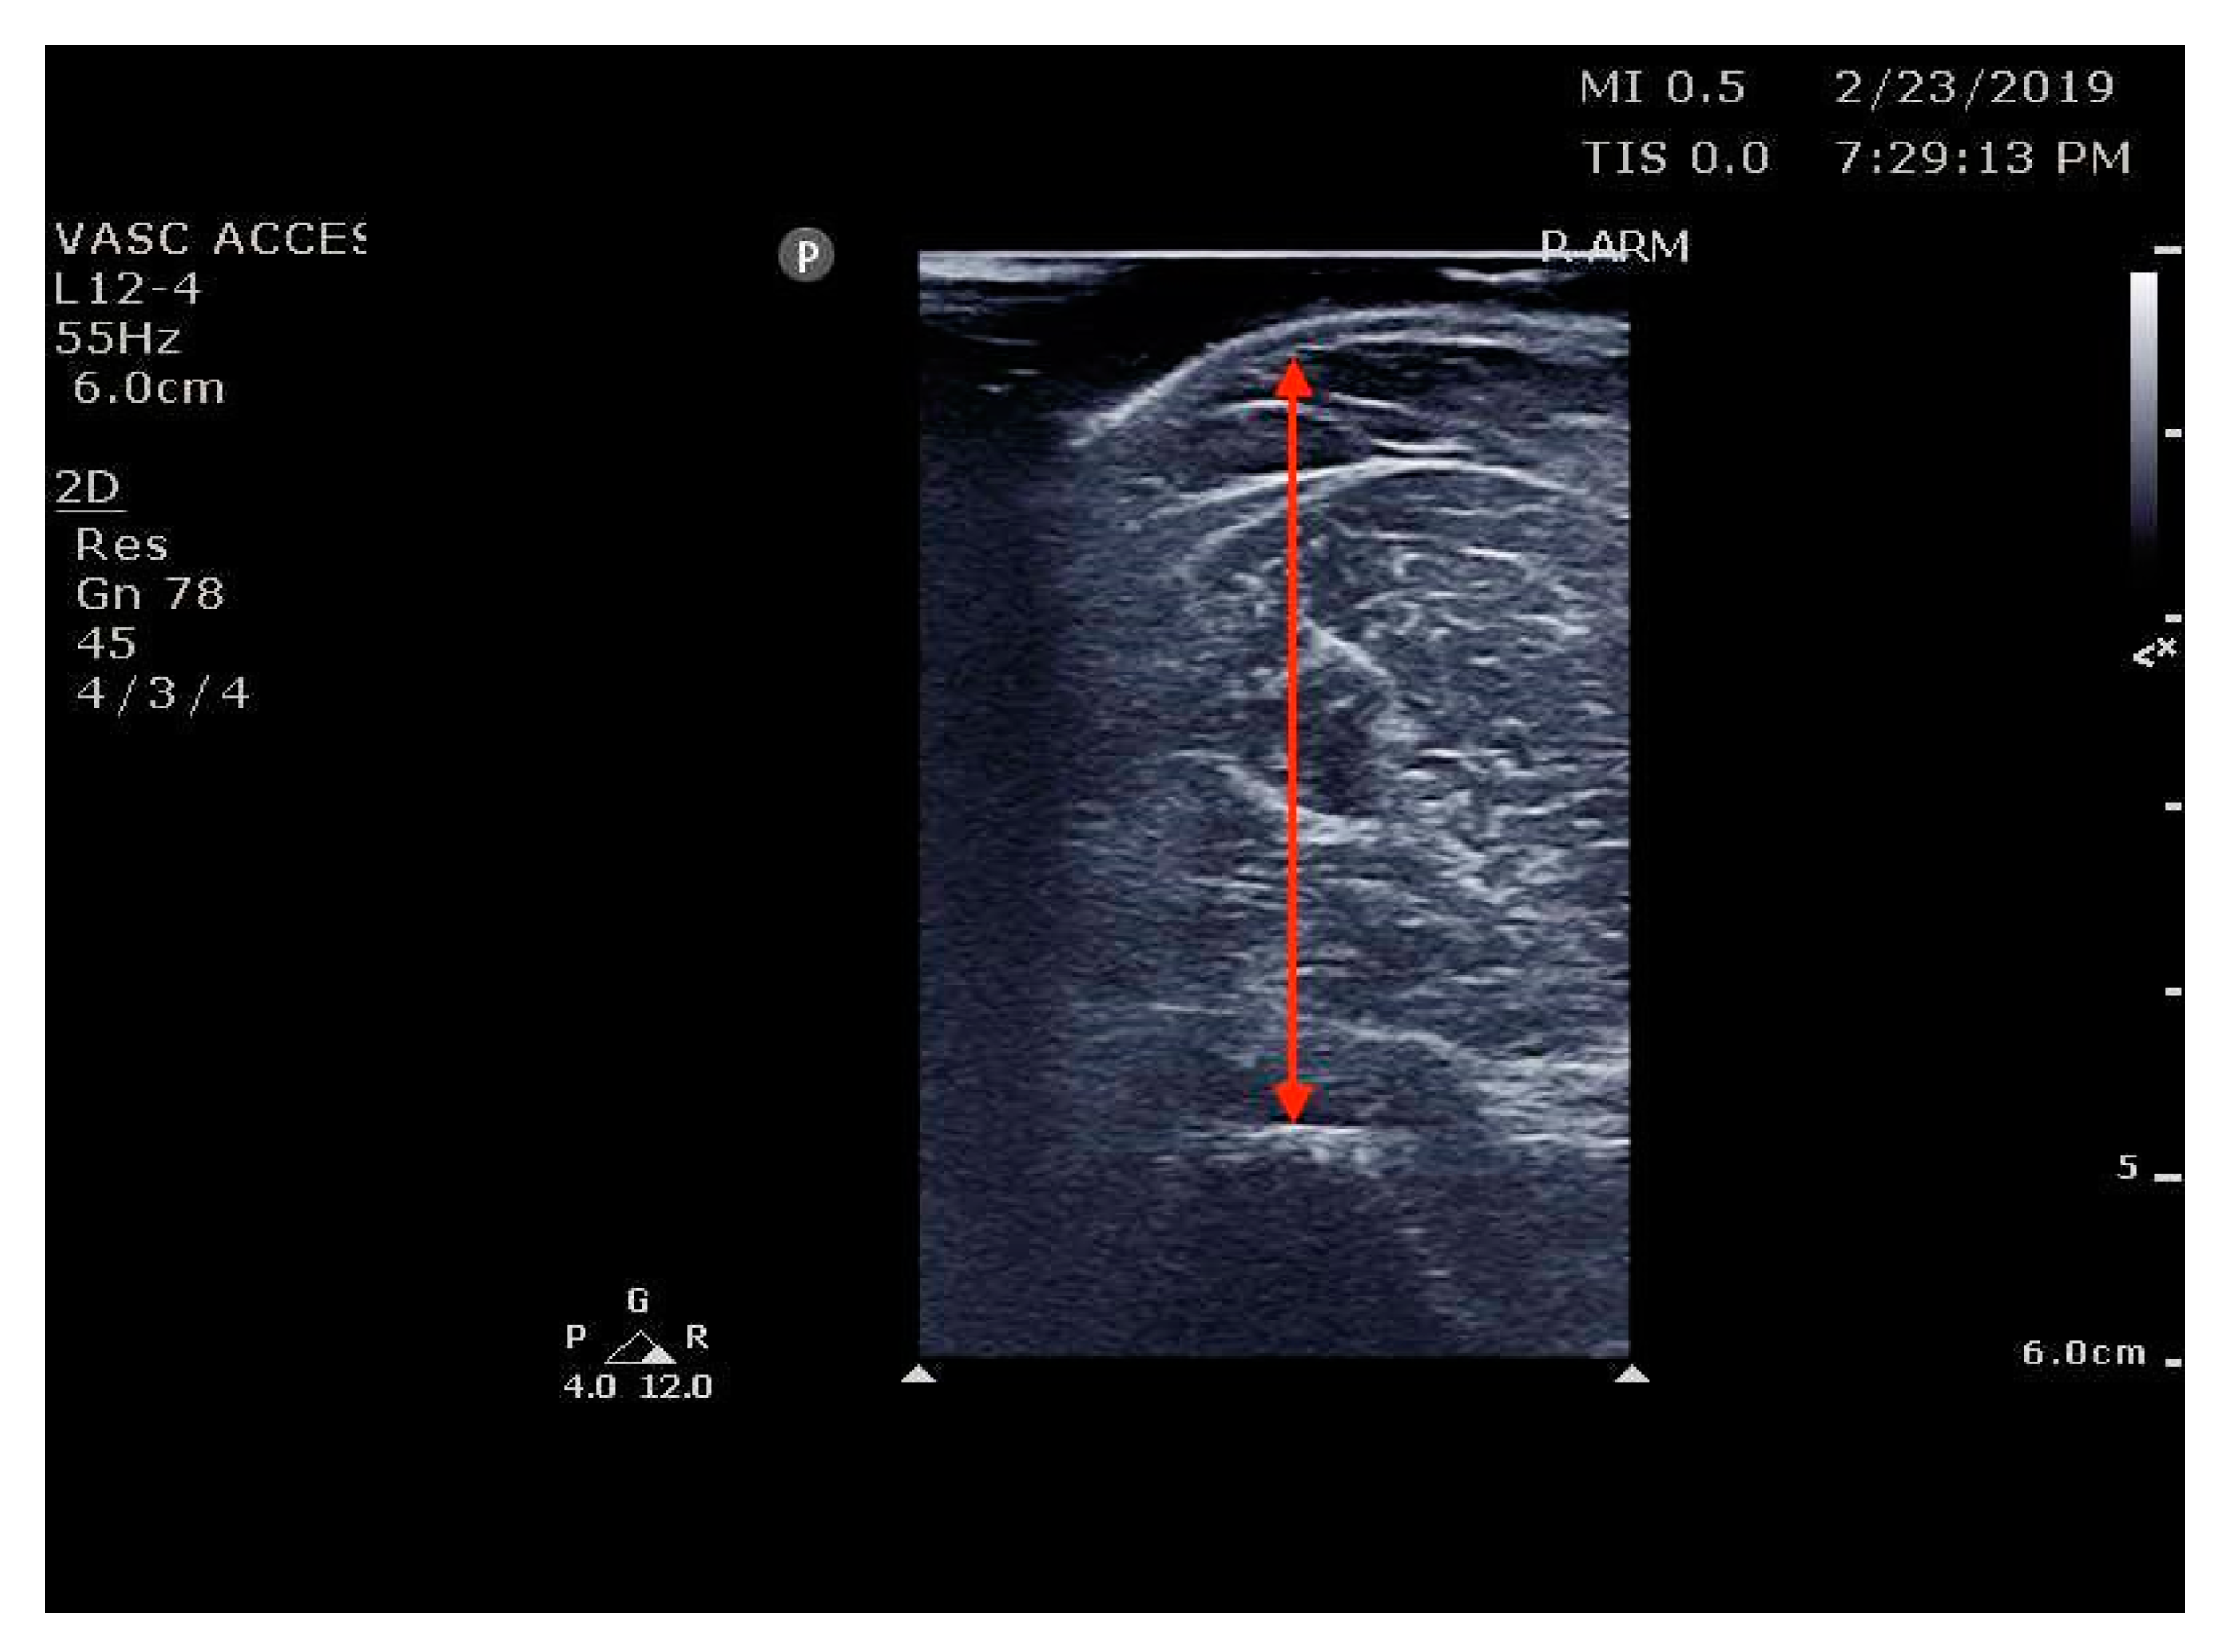

The Principal Investigator (PI), co-investigators, and RAs were trained with a 2 h lecture and a 4 h hands-on training session given by a POCUS-certified instructor from the Division of Emergency Ultrasound. Post-training, the intraclass correlation (ICC) [25,26] of sonographic measurements of the biceps and thigh muscle between the research team was 0.92. The research team included two emergency physicians, three EM Advanced practice practitioners with ultrasound experience, three EM ultrasound fellows, and two geriatric research fellows who are emergency physicians (Figure 1 and Figure 2).

Figure 1.

Ref. [33] Bicep brachii thickness measurement.

RAs asked participants about their history of falls and fall-risk factors and then measured the thickness of upper and lower limb muscles using POCUS as well as measured grip strength, and they asked the patients’ cooperation to do the Timed up and go (TUG) test. We used the standard POCUS ultrasound machines (Mindray, TE7, 2019) and linear transducer with a frequency range of 2–8 MHz available in the ED to measure the muscle thickness of each patient’s upper and lower extremities on their dominant side. Following Perkisas, the biceps landmark was the midpoint between the acromion process and the elbow crease at the anatomical position [29,40]. The thigh muscle (rectus femoris/vastus intermedius) landmark was the midpoint between the anterior superior iliac spine and the proximal patella at the anatomical position [41,42]. Participants were instructed to lie down on the couch with their hips and knees extended against the couch. A copious amount of water-soluble gel was applied to the skin to avoid pressure on the muscle. The RA measured the muscle by including the muscle belly and fascia and excluding subcutaneous adipose tissue or skin and stored the images in the protected hospital cloud data storage system.